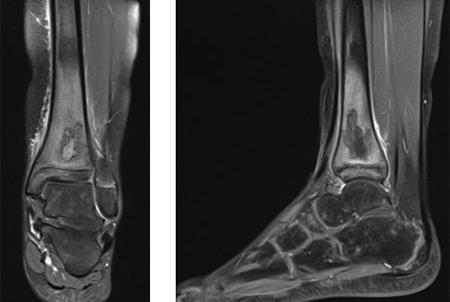

43 Riksfot – fot- och fotledskirurgi